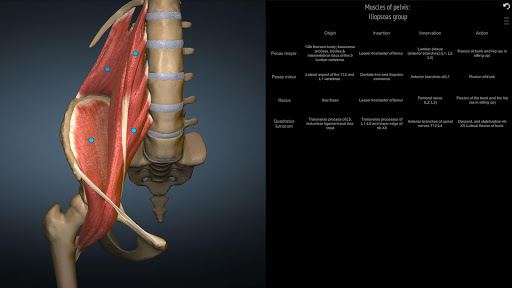

A true and totally 3D app for studying human anatomy, built on an advanced interactive 3D touch interface.

★ Muscles